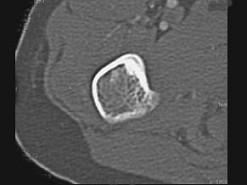

问题 男,28岁,右上肢疼痛,夜间加重,服用止痛药可缓解,结合图像,最可能的诊断是 ( )

选项 A、骨囊肿 B、成骨细胞瘤 C、骨软骨瘤 D、骨样骨瘤 E、骨瘤

答案 D